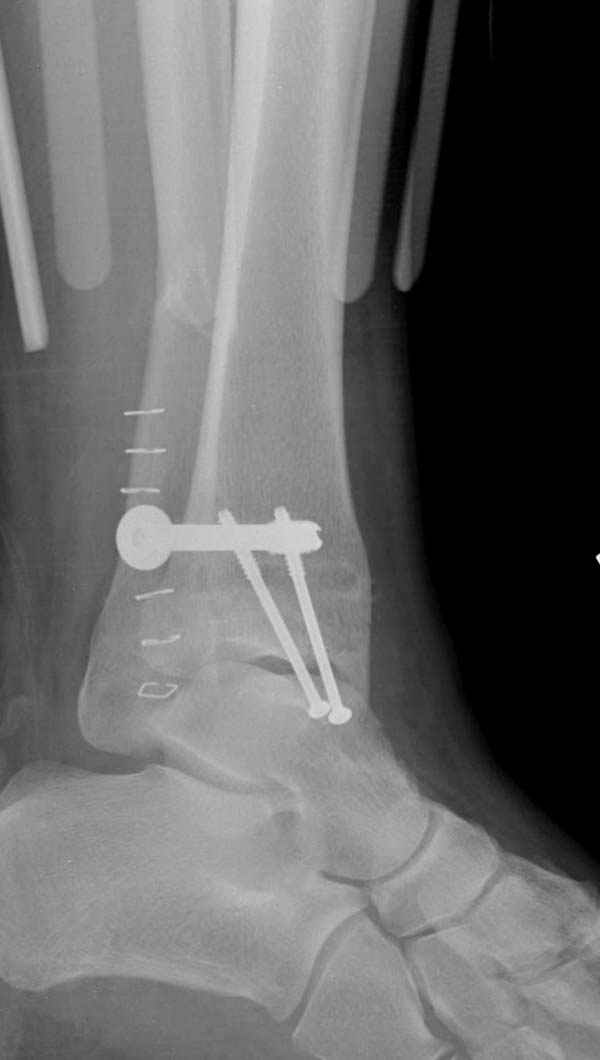

Ниже рентгенограммы

До операции 28 июля

Операция 29 июля

Через месяц

Боковой через месяц

15 ноября прямой

15 ноября боковой

15 ноября трехчетвертной

12 января прямой

12 января боковой

12 января трехчетвертной

Риторический вопрос - в каком руководстве рекомендован такой способ остеосинтеза наружной лодыжки?

Очевидно, такой результат операции был запрограммирован. При невосстановленной длине и практически нефиксированной малоберцовой кости (этот кортикальный винт - как карандаш в стакане), при неустраненном подвывихе, невправленной и тоже нефиксированной внутренней лодыжке нет стабильной вилки сустава. Если такую операцию сделать даже сразу, а не через 4 месяца, то результат ожидаем

тот же.

Если до сих ничего не сделано, с артродезом сустава в данный момент я бы повременил, на выставленных январских снимках хорошо сохранившийся сустав, а в "мортиз" (трехчетвертной) и на боковых снимках не менее 5 мм укорочение малоберцовой кости. Косые переломы лучше фиксировать пластинами, как то мы разбирали случай, где было отмечено, что это закон "таранная кость всегда следует за малоберцовой".